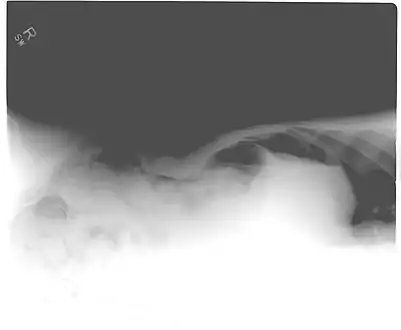

Pneumoperitoneum seen on X-ray with the patient lying on his left side.